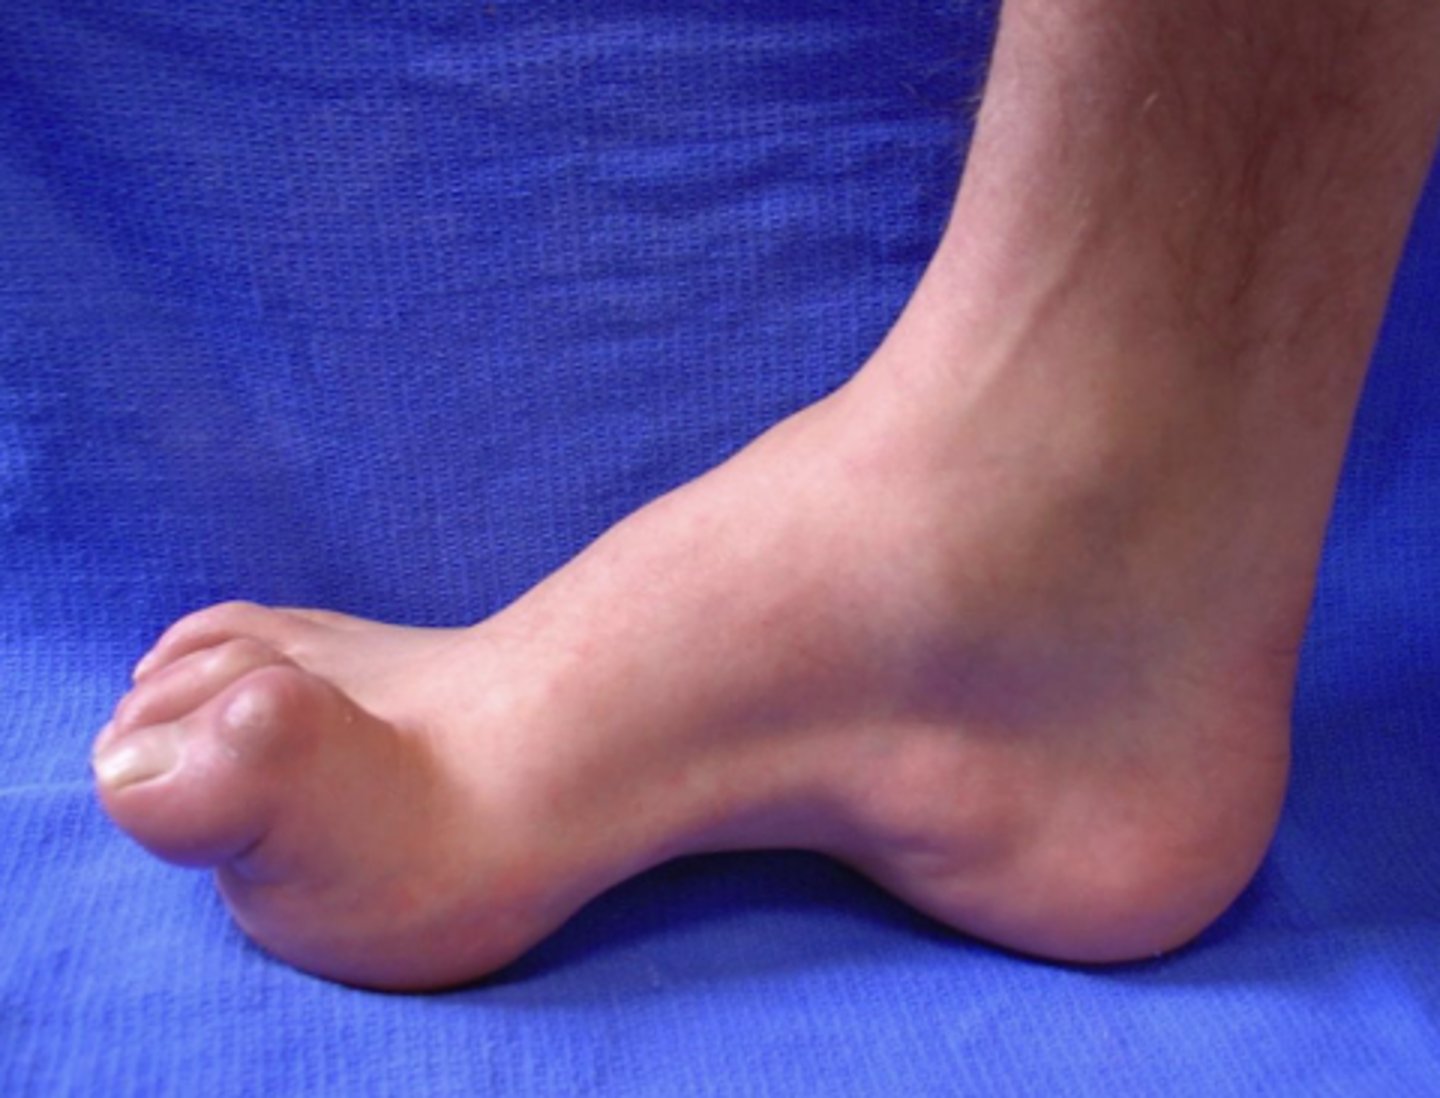

What are the characteristics of Charcot-Marie-Tooth (CMT) disease?

typically in 1st or 2nd decade of life, + family history, demyelinating > axonal

What are the classic physical signs of Charcot-Marie-Tooth (CMT) disease?

High arches, hammer toes, distal atrophy, foot drop, and hyporeflexia or areflexia.

What is the treatment of CMT?

PT/OT, Bracing (ankle-foot orthotics)